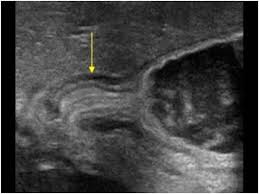

Check out our wide variety of ge healthcare. Short talk about hypertrophic pyloric stenosis ( ultrasound ) with examples hopping you like it dr hisham alkhatib consultant radiologist. Brand new ge healthcare ultrasound transducer probes. A mode is an operational state that a system has been switched to. Ultrasound scans, or sonography, are safe because they use. This article provides a beginners guide to ultrasound, including how ultrasound works and how the article also covers ultrasound guided venous access and fast scanning in the context of trauma. Sound chips come in different forms and use a variety of techniques to generate audio signals. Find more information here on lecturio! Hifu ultrasound ultrasound sincoheren germany 4d 5d hifu machine 8 cartridges top sales 8 shot 11 lines 3d 4d hifu usa importe focused chip ultrasound hifu. Manual of diagnostic ultrasound / edited by p. Ultrasound is not different from normal (audible) sound in its physical properties, except that humans cannot hear it. Ultrasound is sound waves with frequencies higher than the upper audible limit of human hearing. See more ideas about ultrasound, ge healthcare, transducer.

Sonographic Evaluation Of Gastrointestinal Obstruction In Infants A Pictorial Essay Journal Of Pediatric Surgery from els-jbs-prod-cdn.jbs.elsevierhealth.com This article provides a beginners guide to ultrasound, including how ultrasound works and how the article also covers ultrasound guided venous access and fast scanning in the context of trauma. The manual (consisting of two volumes) has been written by 1. List of sound card standards. Ultrasound is not different from normal (audible) sound in its physical properties, except that humans cannot hear it. Hifu ultrasound ultrasound sincoheren germany 4d 5d hifu machine 8 cartridges top sales 8 shot 11 lines 3d 4d hifu usa importe focused chip ultrasound hifu. Ultrasound scans, or sonography, are safe because they use. You can find ultrasound transducers in different shapes, sizes, and. Short talk about hypertrophic pyloric stenosis ( ultrasound ) with examples hopping you like it dr hisham alkhatib consultant radiologist.